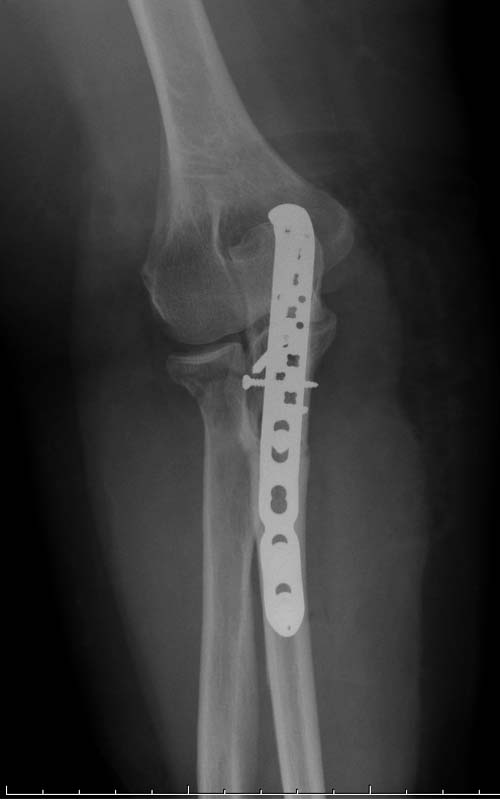

Здесь представлены несколько случаев и как видно больше больных с серьезными повреждениями, чем изолированные..

В первом случае перелом Монтеджи, где доперационно сделано оценка положения головки к остальным элементам под рентгеном. Учитывая правильность взаимотношении произведена фиксация только локтевого отростка, Второй случай, заменена на протез, и третий, кроме фиксации головки - реконструкция capitellum латерального мыщелка.